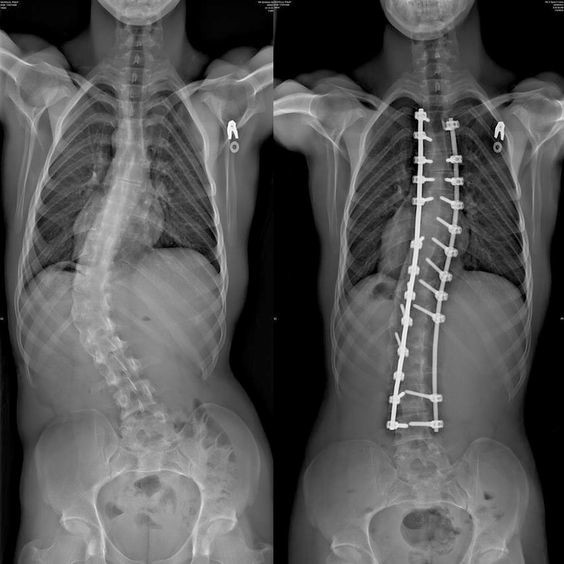

16. 6 лет назад мне сделали операцию по выпрямлению позвоночника, вот результат «до и после»